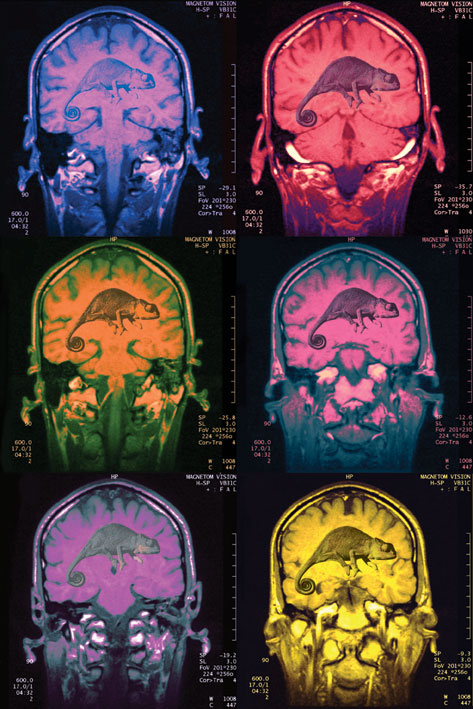

These findings amount to the greatest change in our understanding of the human brain in 400 years. It is the discovery that the adult human brain, rather than being fixed or “hardwired”, can not only change itself but works by changing itself. It is “neuroplastic”: “neuro” for neuron, the nerve cells in the brain, and “plastic” in the sense of adaptable, changeable, malleable. Neuroplasticity is the property of the brain that allows it to change its structure and function in response to what it senses, what it does and even what it thinks and imagines.

The brain is both more resilient and more vulnerable than we had imagined. Just as the senses can develop, so can the pain system, becoming too good for our own good, giving rise to hypersensitivity syndromes and chronic neuropathic pain. Brain scans are now showing that relationships, too, literally mould our brains, for better or for worse.